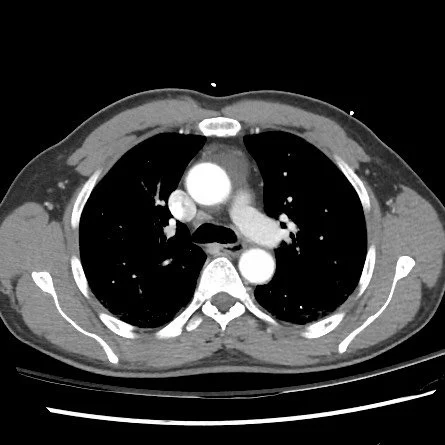

Pericardial Recess

• Spaces within the pericardium formed by reflections of the pericardium

• Can become fluid filled = basically a cyst in the pericardium

• Case courtesy of Andrew Dixon, Radiopaedia.org, rID: 55524 (pericardial recess)